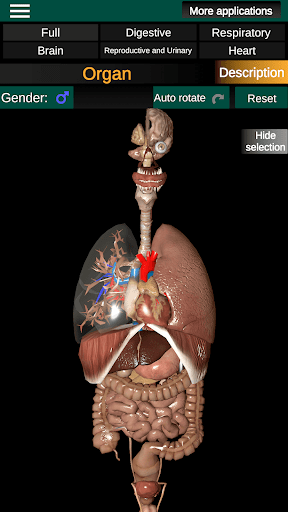

Internal Organs in 3D Anatomy لـ Vodafone Smart N9 Lite

(الأجهزة الداخلية في)

Internal Organs 3D Anatomy 3.4

يمكنك هنا تنزيل ملف حزمة تطبيق أندرويد "Internal Organs 3D Anatomy" الخاصة بجهازVodafone Smart N9 Lite مجانًا، نسخة ملف حزمة تطبيق أندرويد - 3.4 للتحميل على Vodafone Smart N9 Lite اضغط ببساطة على هذا الزر. إنه سهل وآمن. نحن نقدم فقط ملفات حزمة تطبيق أندرويد الأصلية. إذا انتهكت أية مواد موجودة في الموقع حقوقك قم بإبلاغنا من خلال